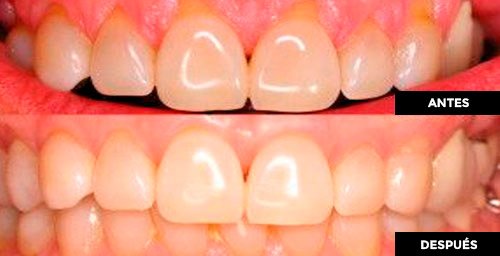

BLANQUEAMIENTO DENTAL

Los dientes amarillentos pueden generar una inquietud estética y falta de confianza al hablar y sonreír.

El consumo de café, vino tinto, fumar e incluso algunos alimentos, pueden pigmentar los dientes.

Los estudios muestran que las personas que confían en su sonrisa llevan una vida en general más saludable.

El blanqueamiento aclara la tonalidad de los dientes para lograr una sonrisa más estética y saludable.

Ofrecemos varias opciones de sistemas de blanqueamiento dental con láser, a un precio económico y con resultados exitosos.